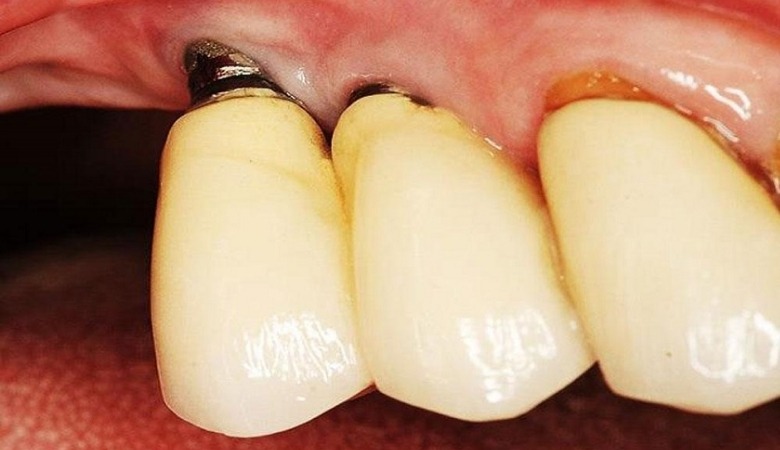

Trụ implant không đạt tiêu chuẩn gây kích ứng

Chất liệu được sử dụng để chế tạo trụ implant đóng vai trò then chốt trong sự thành công của ca cấy ghép. Titanium là vật liệu được chứng minh là tương thích sinh học tốt nhất với cơ thể người và thường được sử dụng để sản xuất trụ implant cao cấp. Tuy nhiên, các loại trụ implant giá rẻ thường không được làm từ titanium nguyên chất mà có thể pha lẫn các tạp chất khác như niken, chì, kẽm…

Những tạp chất này có thể gây ra các phản ứng dị ứng và kích ứng trong khoang miệng, dẫn đến tình trạng viêm nướu, sưng tấy, đau rát và khó chịu kéo dài. Trong một số trường hợp nghiêm trọng, cơ thể có thể phản ứng mạnh mẽ, dẫn đến việc đào thải trụ implant. Việc sử dụng vật liệu không rõ nguồn gốc, không được kiểm định chất lượng cũng là một nguy cơ tiềm ẩn gây hại cho sức khỏe.